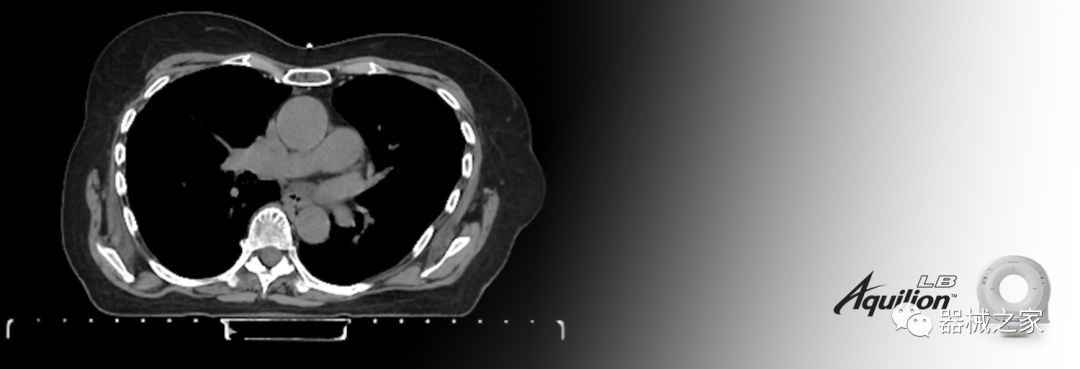

Aquilion LB專為滿足腫瘤學挑戰(zhàn)而設(shè)計,同時優(yōu)先考慮患者護理。Aquilion LB的內(nèi)徑為90 cm,能夠幫助復雜的患者設(shè)置并提高患者的舒適度。CT模擬定位可以輕松鏡像放射治療定位,更加自信。該系統(tǒng)采用0.5 mm x 16排(32層)PUREViSION探測器技術(shù),70 cm視野,AIDR 3D和SEMAR技術(shù)。